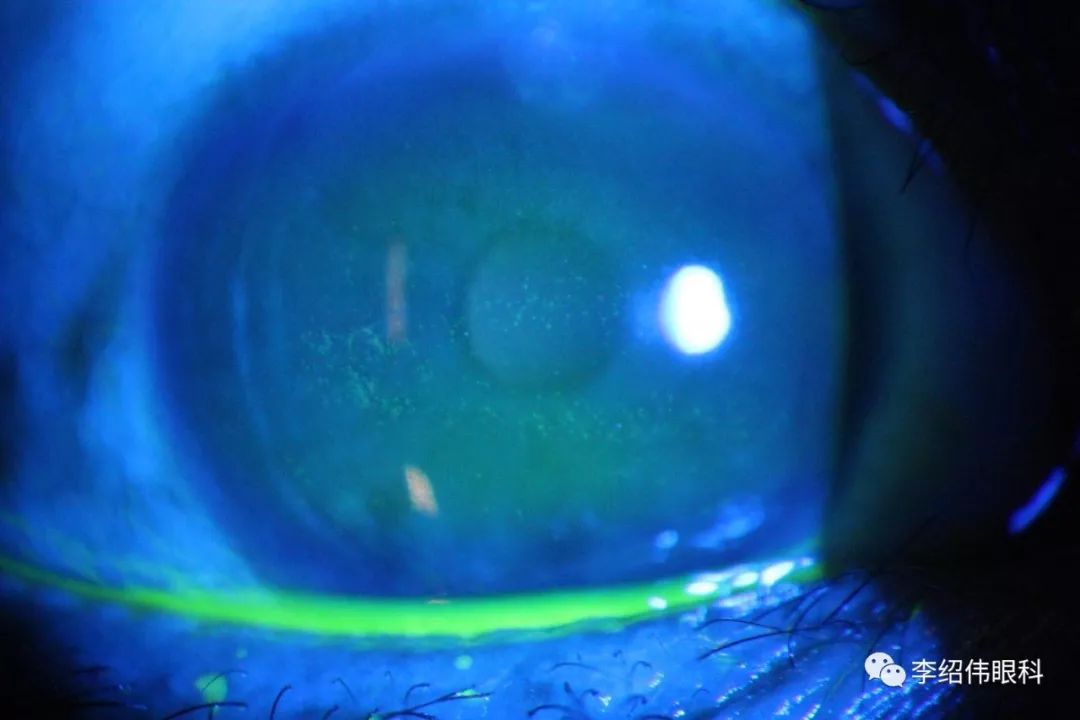

图一. 一周后复查,溃疡愈合,但是DLK依旧,不过没有明显炎症反应,患者感觉明显好转,视力Vod1.0,Vos 1.2。

图二. 一周后复查,没有变化,无充血,但是层间沙洋DLK依然存在。于是改成主要治疗DLK。典必殊眼水Q2h,加替沙星QN, ACV0。4BiD。

图三. 一周后复查,完全没有症状,但是层间DLK还是存在,不像活动性。此时因为病情已经稳定,就补查了睑板腺照相。没有发现明显异常,给予人工泪液回去观察。